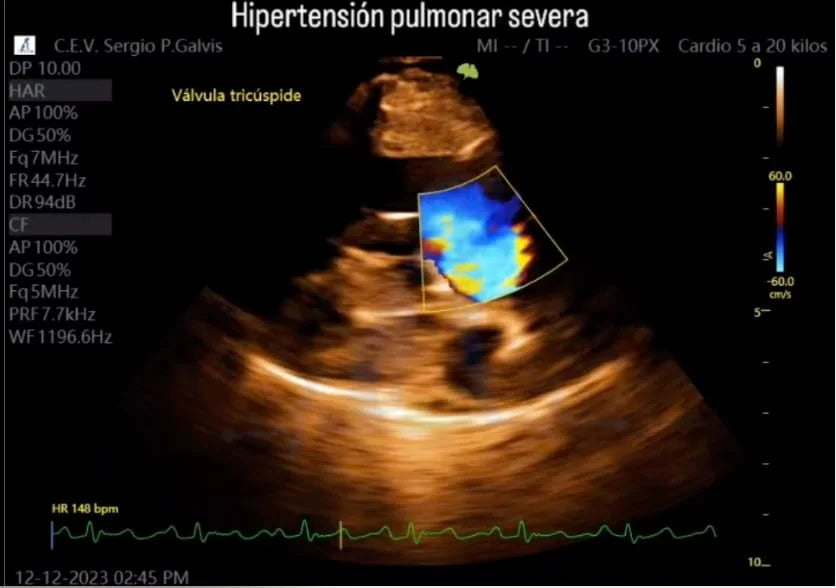

Para los veterinarios, el diagnóstico de hipertensión pulmonar es un desafío, ya que no puede ser detectado mediante un examen físico convencional. Aquí es donde entra en juego la importancia del ultrasonido doppler, una herramienta que permite evaluar la circulación de sangre y la presión en las arterias pulmonares de manera no invasiva. Gracias a la ecografía, los veterinarios pueden medir con precisión el flujo sanguíneo y detectar la presencia de hipertensión

Importancia del Diagnóstico Temprano: Los síntomas pueden pasar desapercibidos hasta etapas avanzadas. El ultrasonido Doppler es fundamental para una detección precisa y oportuna.

En este contexto, los equipos de ecografía doppler como los ecógrafos VINNO ofrecen una solución de vanguardia para los especialistas en veterinaria. Estos ecógrafos permiten visualizar con claridad la circulación pulmonar y cuantificar los niveles de presión en tiempo real, brindando a los veterinarios la capacidad de detectar la hipertensión pulmonar con mayor precisión y ofrecer un tratamiento más adecuado.

Los avances en imagenología veterinaria han permitido un diagnóstico más preciso y oportuno de esta enfermedad. Equipos como los ecógrafos VINNO no solo facilitan la detección de hipertensión pulmonar, sino que también ofrecen herramientas avanzadas para evaluar otras patologías cardíacas y respiratorias, mejorando la capacidad de los veterinarios para brindar un tratamiento efectivo y personalizado.